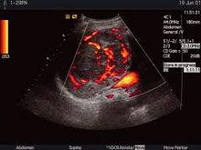

Гепатоцеллюлярный рак – злокачественное новообразование, наиболее распространенное среди опухолей печени. Это онкологическое заболевание находится на шестом месте по частоте обнаружения всех случаев рака и дает очень высокую смертность – до девяноста процентов заболевших. Одной из причин такого соотношения является связь между вирусным гепатитом В и ГЦР.

Заболеваемость гепатитом С также является одной из причин диагностики гепатоцеллюлярного рака. Это ставит гепатит на первое место в числе факторов, способствующих развитию ГЦР.

Относится к факторам риска также цирроз печени, контакт с химическими соединениями, содержащими хлор и наследственную предрасположенность.